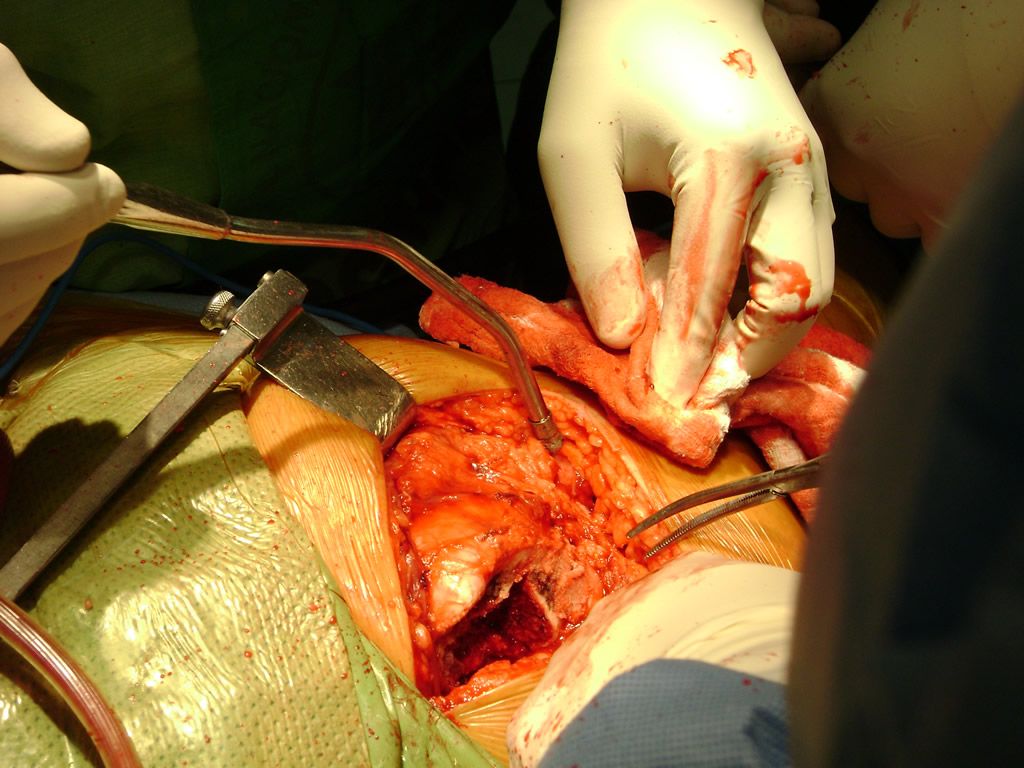

Cirugías de Peroné y Tibia

Debido a la fina cobertura de piel que recubre la tibia y el peroné, las fracturas generalmente son abiertas, es decir, el hueso roto rasga la piel, atravesándola. Las fracturas de tibia y peroné generalmente se producen por un fuerte impacto o torsión.